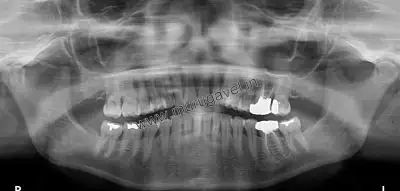

Preoperative X-Ray

It shows that periapical lesion in the rc treated tooth in both upper & lower left molar.